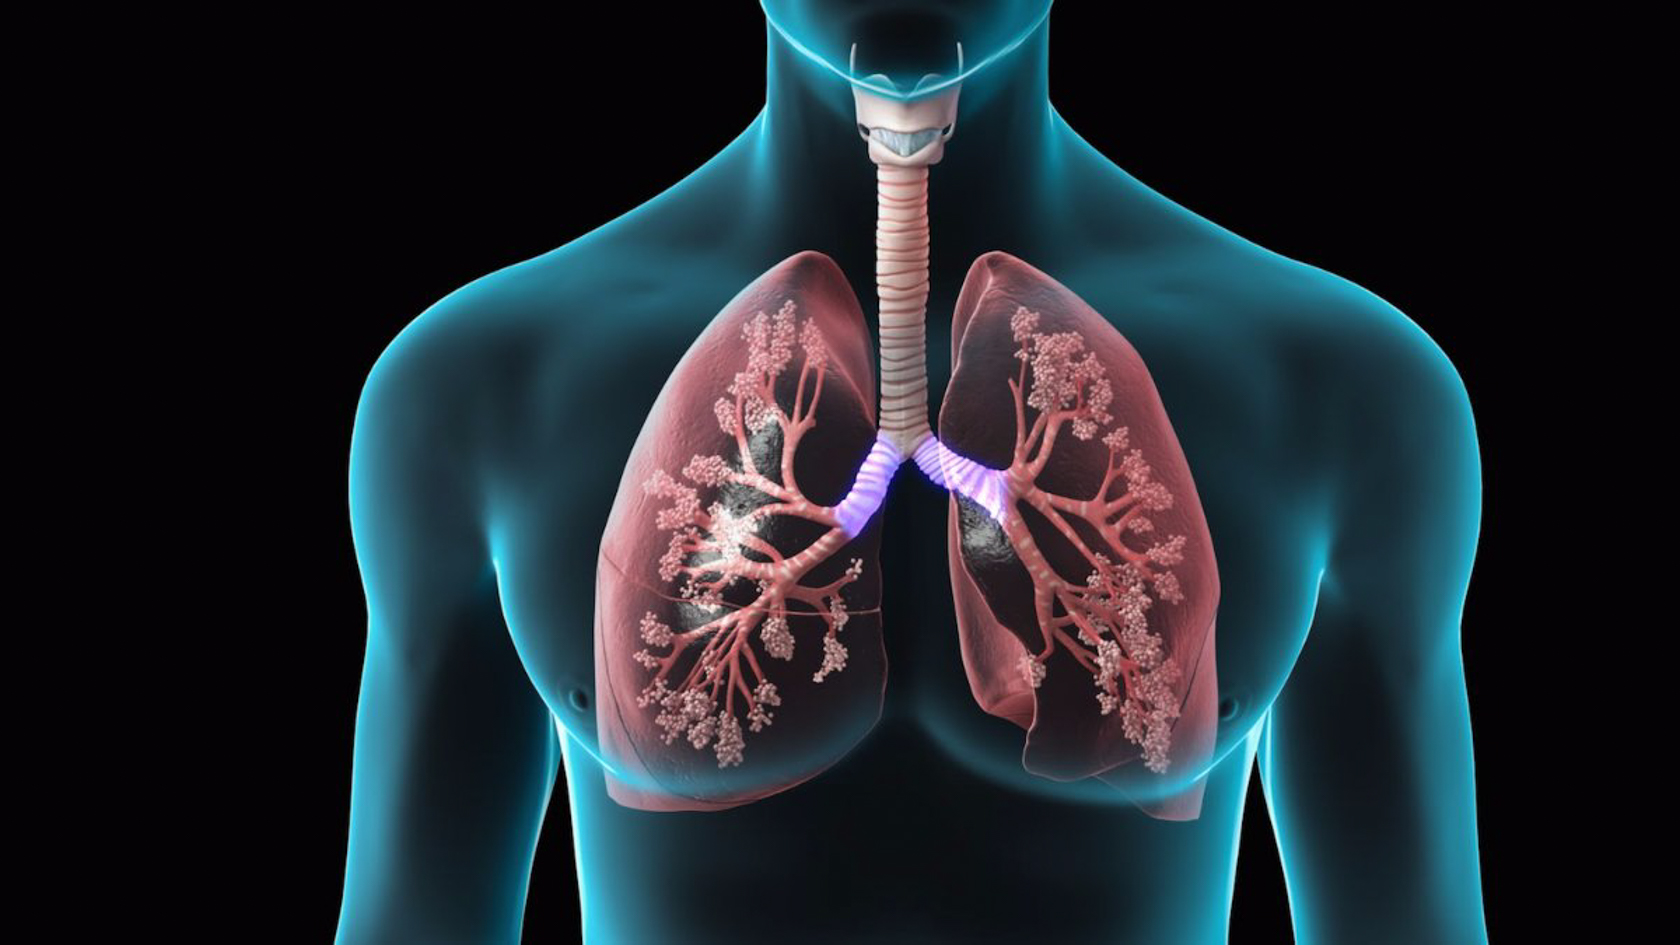

Дыхательная система выполняет жизненно важную функцию — обеспечение клеток организма кислородом и освобождение их от углекислого газа, являющегося конечным продуктом …

Дыхательная система (дыхательный аппарат), systema resperatorium, состоит из дыхательных путей и парных дыхательных органов - легких . Дыхательные пути …

Основной механизм регулирования дыхания — центральная нервная система . Дыхательный центр регулирует частоту и ритм дыхания .